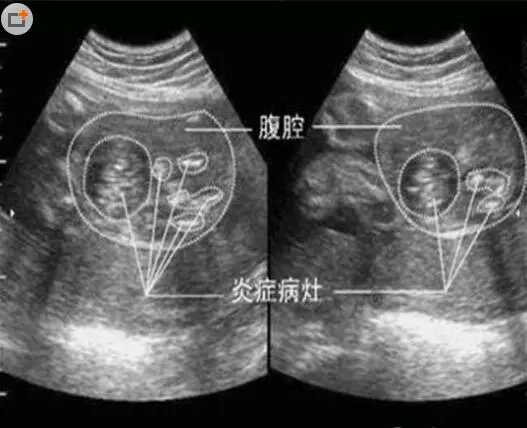

为什么会发生这个现象呢?原来,发生这个现象是因为羊水过少,胎儿是过期妊娠,他在子宫里的大便使得羊水都被严重污染,他自己也吸入了污染的羊水和粪便,现在肺里也充满了粪便的颗粒,使得宝宝没办法呼吸,还好最后抢救回来,经过后续的治疗他也渐渐恢复健康。